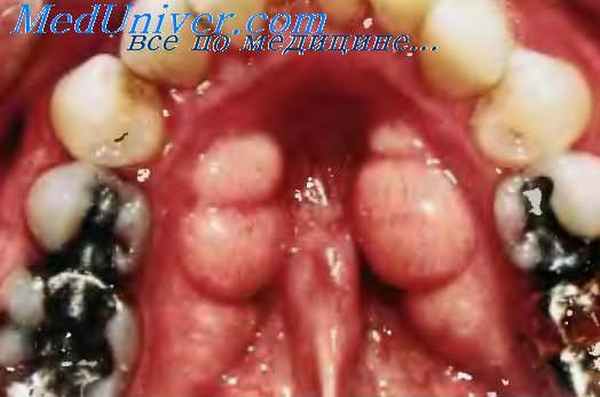

Гигантоклеточная фиброма имеет вид розовой папулы или узелка на широком основании, с гладкой или слегка зернистой поверхностью. Это разновидность ирритационной фибромы, она диагностируется в основном при гистологическом исследовании, которое обычно выявляет множество больших многоядерных фибробластов звёздчатой формы, свободно расположенных в соединительной ткани, богатой кровеносными сосудами. Гигантоклеточную фиброму наблюдают в возрасте до 35 лет, и наиболее часто она локализуется на десне, языке и нёбе. Лечение заключается в хирургическом иссечении. Рецидивы наблюдают редко.

Валики полости рта

- Симметричные фибромы появляются рядом с третьими молярами на поверхности нёба и на десне. Обладают плотной консистенцией и формой, напоминающей бобовые. Такого типа новообразования – не истинная опухоль, а итог увеличения десны в объемах, этот патологический процесс протекает с образованием рубцов.